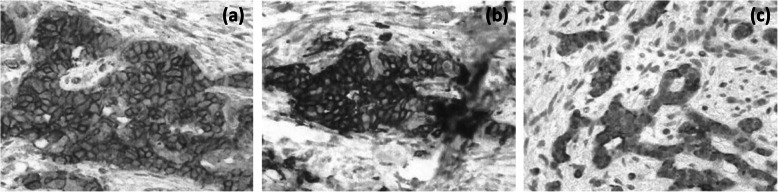

Under a diagnosis of primary cholangiocarcinoma (CCA) of the DBD, a subtotal stomach-preserving pancreaticoduodenectomy was performed. Neither peritoneal dissemination nor lymph node metastases were found during the operation. Macroscopically, an irregularly shaped nodular tumor was found in the DBD (Fig. 4). Microscopically, the lesion was seen to be composed of predominantly well-differentiated tubular AC in the superficial layer of the tumor, admixed with neuroendocrine carcinoma (NEC) in the deeper portion (Fig. 5), indicating a diagnosis of MANEC of the DBD. While the AC component shows papillary growth toward the lumen of the bile duct, the NEC component had infiltrated into the muscle layer, with vascular and neural invasion. Atypical epithelium was found extensively in the superficial epithelium and accessory glands of the CBD, but no malignancies were found in the gallbladder, cholecystic duct, papilla of Vater, pancreas, or duodenum; based on this, the final pathological diagnosis was MANEC of the CBD, Pat Bi, fm, pPanc0, pDu0, pHM0, pEM0, tubular, well-differentiated tubular AC>NEC, INF β, int, ly0, v0, pm1. No lymph node metastases were found. After immunohistochemical staining, NEC components were diffusely positive for synaptophysin and CD56, and the MIB-1 index was 30% (Fig. 6). In both components, p16 was positive and p53 was negative. Additionally, the NEC component was strongly positive for SSTR2, SSTR5, and mammalian target of rapamycin (mTOR) (Fig. 7).

The treatment algorithm for MANEC is not well established [ref. 7–ref. 9]. Surgery may be a mainstay for the treatment of MANEC, and adjunctive therapy with chemotherapy, radiotherapy, and somatostatin analogs can be considered according to the NEC type [ref. 7–ref. 9]. The chemotherapy regimen selection for MANEC remains a major clinical dilemma, since it is complicated by a mixture of distinctive malignant histologies. It is reasonable to treat MANEC in accordance with the more aggressive component of the tumor. MANECs containing a well-differentiated NET component and AC component should be treated as ACs. MANECs containing a poorly differentiated NEC component should be treated as NECs. A NEN shown to possess the receptor for somatostatin (SSTR) is a good candidate for treatment with a somatostatin analog. In this case, SSTR2 and mTOR were positive in the NEC component upon immunohistochemical staining, indicating the use of somatostatin analogs as adjuvant therapy. Therefore, after tumor resection, the pathological differentiation and diagnosis of NENs is important for chemotherapy [ref. 21]. Adjuvant therapies have been seldom attempted in patients with biliary MANEC because clear, consensus-based evidence is lacking. However, adjuvant chemotherapy may be justified, as recurrent events were noted in 2/9 patients (22.2%) [ref. 9]. In this case, S-1 was administered 3 months postsurgery as adjuvant chemotherapy because the AC component was dominant in the tumor. Further studies are required to tailor chemotherapy strategies and to determine which component to target to obtain the best therapeutic benefits.